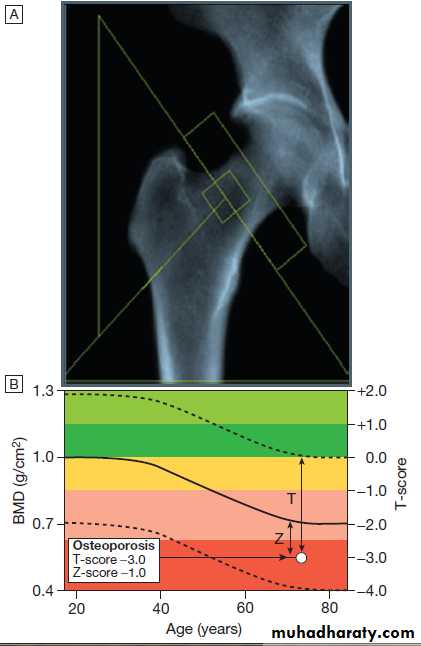

Bone mineral density (BMD)

BMD measurements play a key role in the diagnosis and management of osteoporosis. The technique of choice is dual energy X-ray absorptiometry (DEXA), which is usually performed at the lumbar spine and hip.This technique works on the principle that calcium in bone attenuates passage of X-ray beams through the

tissue in proportion to the amount of mineral present. The greater the amount of bone mineral present, the

higher the BMD value. Most DEXA scanners give a BMD

readout expressed as grams of hydroxyapatite/cm2, and

as a T-score and Z-score value. Osteoporosis is defined by a T-score value of 2.5 or below (shaded red in the figure), whereas osteopenia is diagnosed when the T-score lies between −1.0 and −2.5 (shaded pink).

Fig. Typical output from a dual energy X-ray absorptiometry

(DEXA) scanner.A DEXA scan of the hip.

B Bone mineral density

(BMD) values plotted in g/cm2 (left axis) and as the T-score values (right axis). The solid line represents the population average plotted against age,

and the interrupted lines are ± 2 standard deviations from the average.

The patient shown, aged 72, has an osteoporotic T-score of −3.0 but a Z-score of −1.0, which is within the ‘normal range’ for that age, reflecting the fact that bone is lost with age.